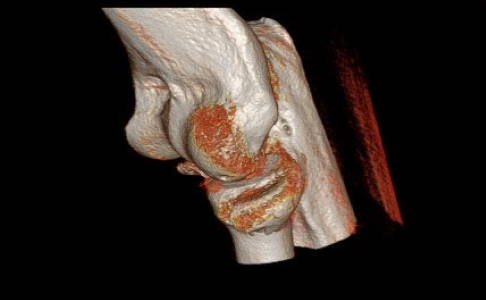

Computertomografie (CT), digitale Volumentomografie (DVT) und Magnetresonanztomografie (MRT)

Ist der Bruch nicht sicher im Röntgenbild zu beurteilen oder liegt ein komplizierter Bruch oder gar eine Zertrümmerung des Radiusköpfchens vor, erfolgt zusätzlich eine Computertomografie (CT)/digitale Volumentomografie (DVT).

Diese Untersuchungen ermöglichen eine eindeutige Einteilung des vorliegenden Bruchs und die Darstellung von möglicherweise vorhandenen knöchernen Begleitverletzungen. Der Bruch des Processus coronoideus ist ein wichtiger Hinweis für ein instabiles Ellenbogengelenk. Dieser knöcherne Vorsprung der Elle stabilisiert das Gelenk neben dem Radiuskopf nach vorne.